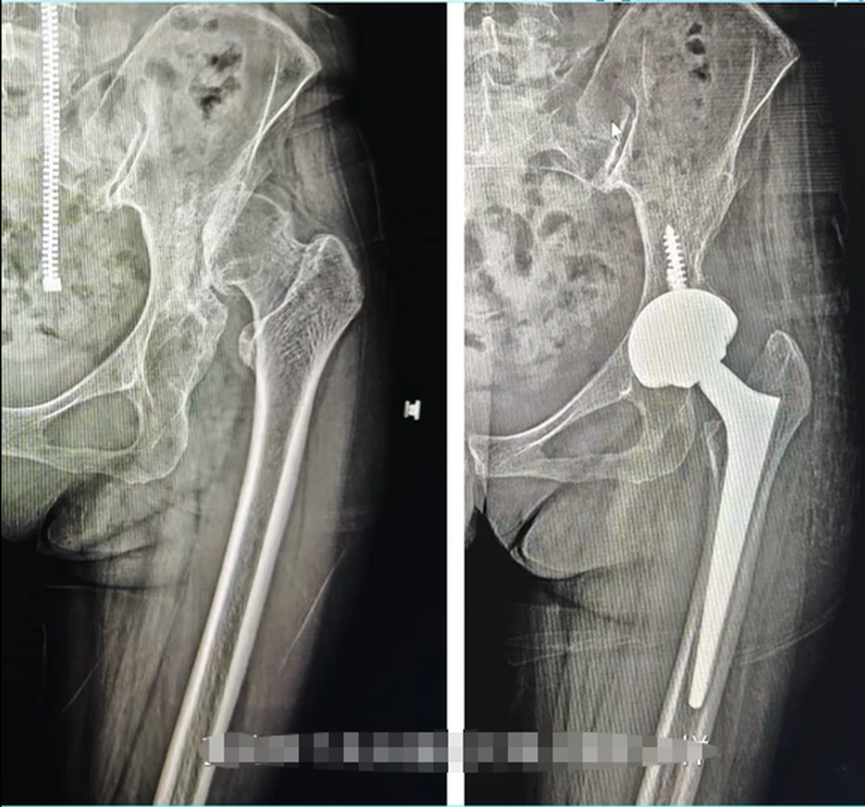

一次偶然的机会,姜女士在网上看到与自己病情相似的患者,在济南关节外科医院通过“不截骨”方案成功完成髋关节置换,便立刻带着家人奔赴济南求医。入院后,医院为其开展了全面细致的检查,围绕姜女士“不截骨”的核心诉求,手术团队反复研讨评估,最终确定采用VTS机器人辅助髋关节置换的手术方案,既能保证手术的安全精准,又能减少创伤。

术前,机器人依托影像学数据,为姜女士量身定制了手术规划,精准锁定假体植入位置与角度;术中,医生借助机器人实时导航与毫米级精准计算,顺利完成关节复位、假体植入等一系列复杂操作,全程无需截骨,手术精准度控制在0.1毫米,最终手术圆满成功。

“术后第二天我就能下地活动了,每天跟着医护人员指导的方案锻炼,一个星期就明显好转。”得益于“不截骨”微创方案、机器人精准辅助,再加上医院成熟的快速康复体系与专业疼痛管理模式,姜女士的恢复速度远超预期。如今三个月过去,她的髋关节功能已完全恢复,可正常行走、回归日常,复查时更是频频向医护人员点赞:“你们的技术太厉害,真是帮我解决了多年的大难题!”